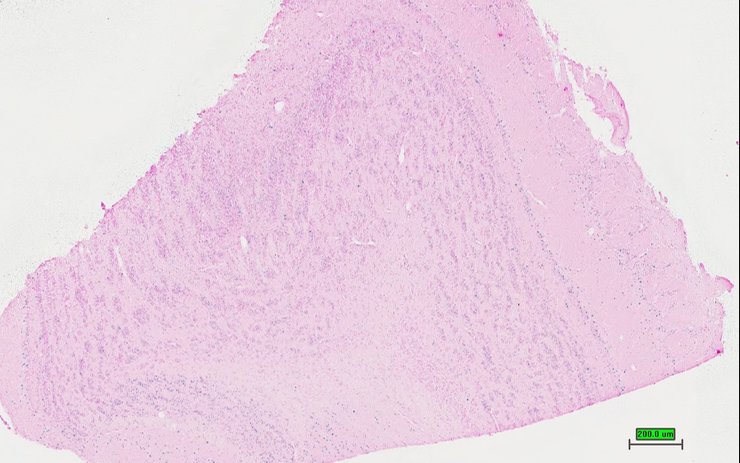

Specimen UC Davis_1885947: postnatal adult; Ubxn2atm1b(EUCOMM)Hmgu/Ubxn2a+ (more )

Structure Level Pattern Image Note

TS28: spleen Present UC Davis_1885947

Specimen UC Davis_1885948: postnatal adult; Ubxn2atm1b(EUCOMM)Hmgu/Ubxn2a+ (more )

TS28: spleen Present UC Davis_1885948